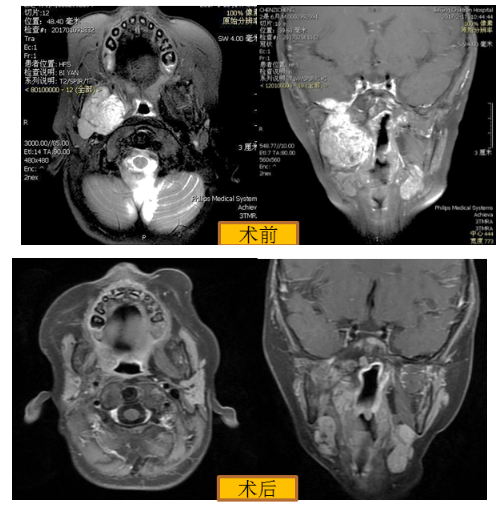

病例4:7个月男孩,右侧面部快速膨隆2个月,不能进食,面部畸形明显,呼吸费力。局部病理活检结果为右侧上颌骨婴儿色素性外胚层瘤,经MDT会诊制定手术方案,由口腔科、耳鼻咽喉头颈外科、神经外科、眼科、介入科联合完成右侧上颌骨肿瘤切除术,患儿顺利康复,恢复正常生活。

图5 右侧上颌骨巨大婴儿色素性神经外胚层瘤